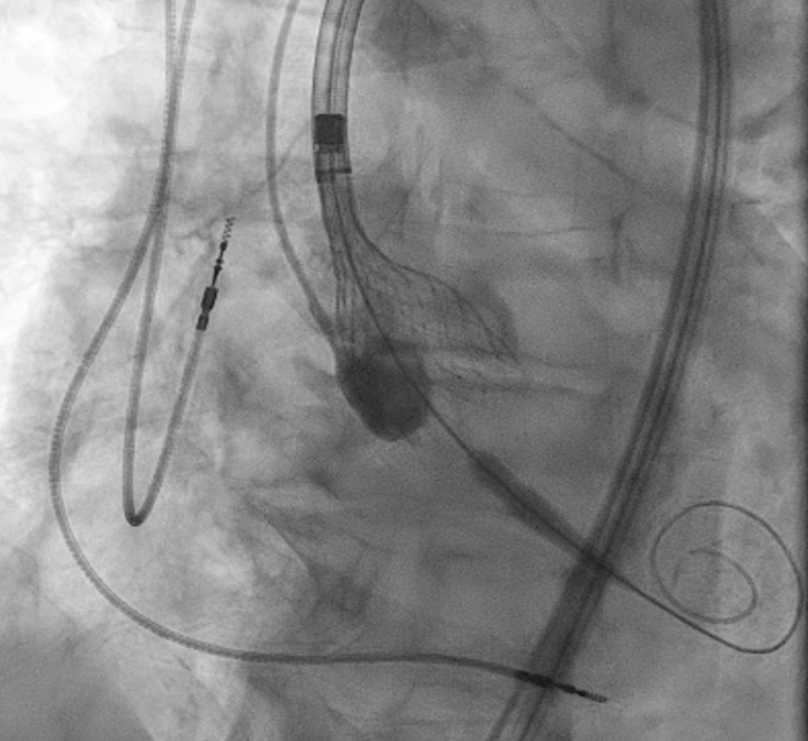

然而,在瓣膜完全展开的瞬间,TEE与造影均提示:26mm Evolut FX瓣膜未固定于主动脉瓣环位置,而是向上移位,脱落于主动脉根部上方区域。

Embolization of Evolut FX above the aortic root

Evolut FX 瓣膜移位栓塞于主动脉根部上方

此时,患者生命体征尚稳定,未出现急性肺水肿、心源性休克等严重血流动力学紊乱——这一关键情况为后续救援策略的制定提供了宝贵时间窗口。

术者立即启动应急方案:通过导管技术将圈套器送至主动脉升部,成功捕获并稳定住移位的瓣膜,避免其进一步栓塞至主动脉弓或头臂干血管,造成致命并发症。

Embolized valve snared and parked in the ascending aorta

移位栓塞瓣膜被捕获并固定于升主动脉